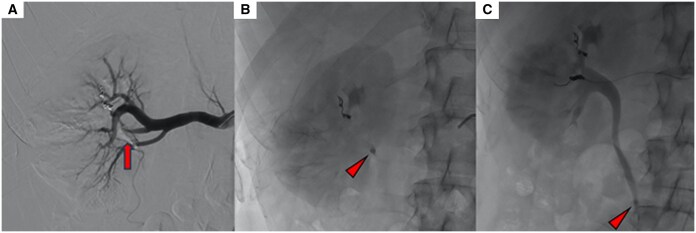

选择性栓塞是稳定患者外伤性肾假性动脉瘤(PSA)的首选治疗方法。n -丁基-2-氰基丙烯酸酯(NBCA)是一种常用的栓塞剂,用于栓塞周围病变。正丁基-2-氰基丙烯酸酯是应用最广泛的栓子材料之一,因为它易于制备,作用迅速,成本效益高。然而,在变得自信并能够安全地使用它之前,它的使用需要一个学习曲线。我们描述了一个病例的肾创伤性PSA栓塞没有明确的术前ct证据动脉-盏瘘,其中NBCA在肾盂的迁移发生在手术过程中。我们报告成功的多学科管理的并发症。

Selective embolization is the treatment of choice for traumatic renal pseudoaneurysm (PSA) in stable patients. N-Butyl-2-cyanoacrilate (NBCA) is an embolic agent frequently used to embolize peripheral lesions. N-Butyl-2-cyanoacrilate is one of the most widely used embolic materials because it is easy to prepare, it acts quickly and is highly cost-effective. Its use, however, requires a learning curve before becoming confident and being able to handle it safely. We describe a case of embolization of a renal traumatic PSA without clear pre-procedural CT-evidence of artero-calyx fistula in which the migration of NBCA in the renal pelvis occurred during the procedure. We report the successful multidisciplinary management of this complication.